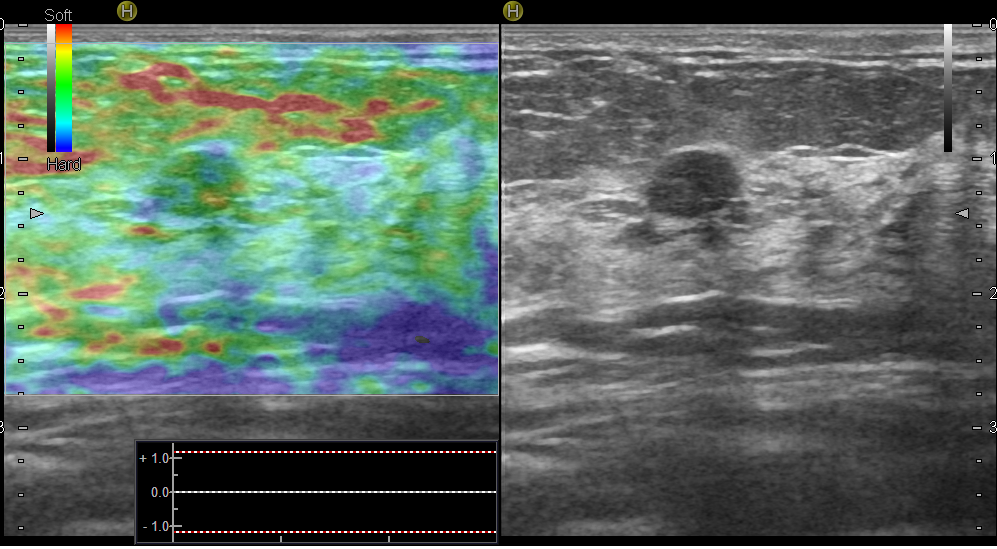

Эластография – инновационная ультразвуковая технология, ее еще называют ультразвуковой пальпацией. Известно, что рак молочной железы имеет более жесткую структуру, чем доброкачественные изменения. Именно эту характеристику и определяет эластография – она измеряет жесткость. Когда врач проводит вам эластографическое исследование – жесткие, а значит подозрительные образования, окрашиваются синим цветом, а эластичные (доброкачественные) – зеленым и желтым. Эластография порой имеет решающее значение.

Рис.10 Эластограмма эластичного образования – фиброаденомы молочной железы

Рис.11 Эластограмма жесткого образования – рака молочной железы